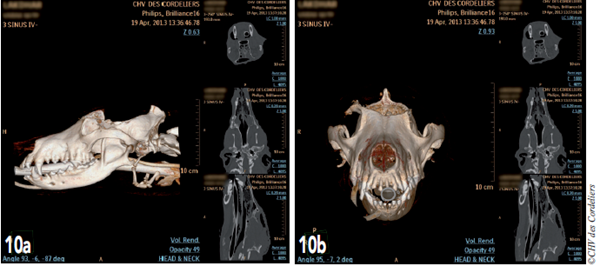

Une acquisition scanner est réalisée avant de placer l’animal en réveil (photo 10).

Photos 10a et 10b : Images tomodensitométriques en post-opératoire immédiat en vue sagittale (a) et en vue frontale (b)